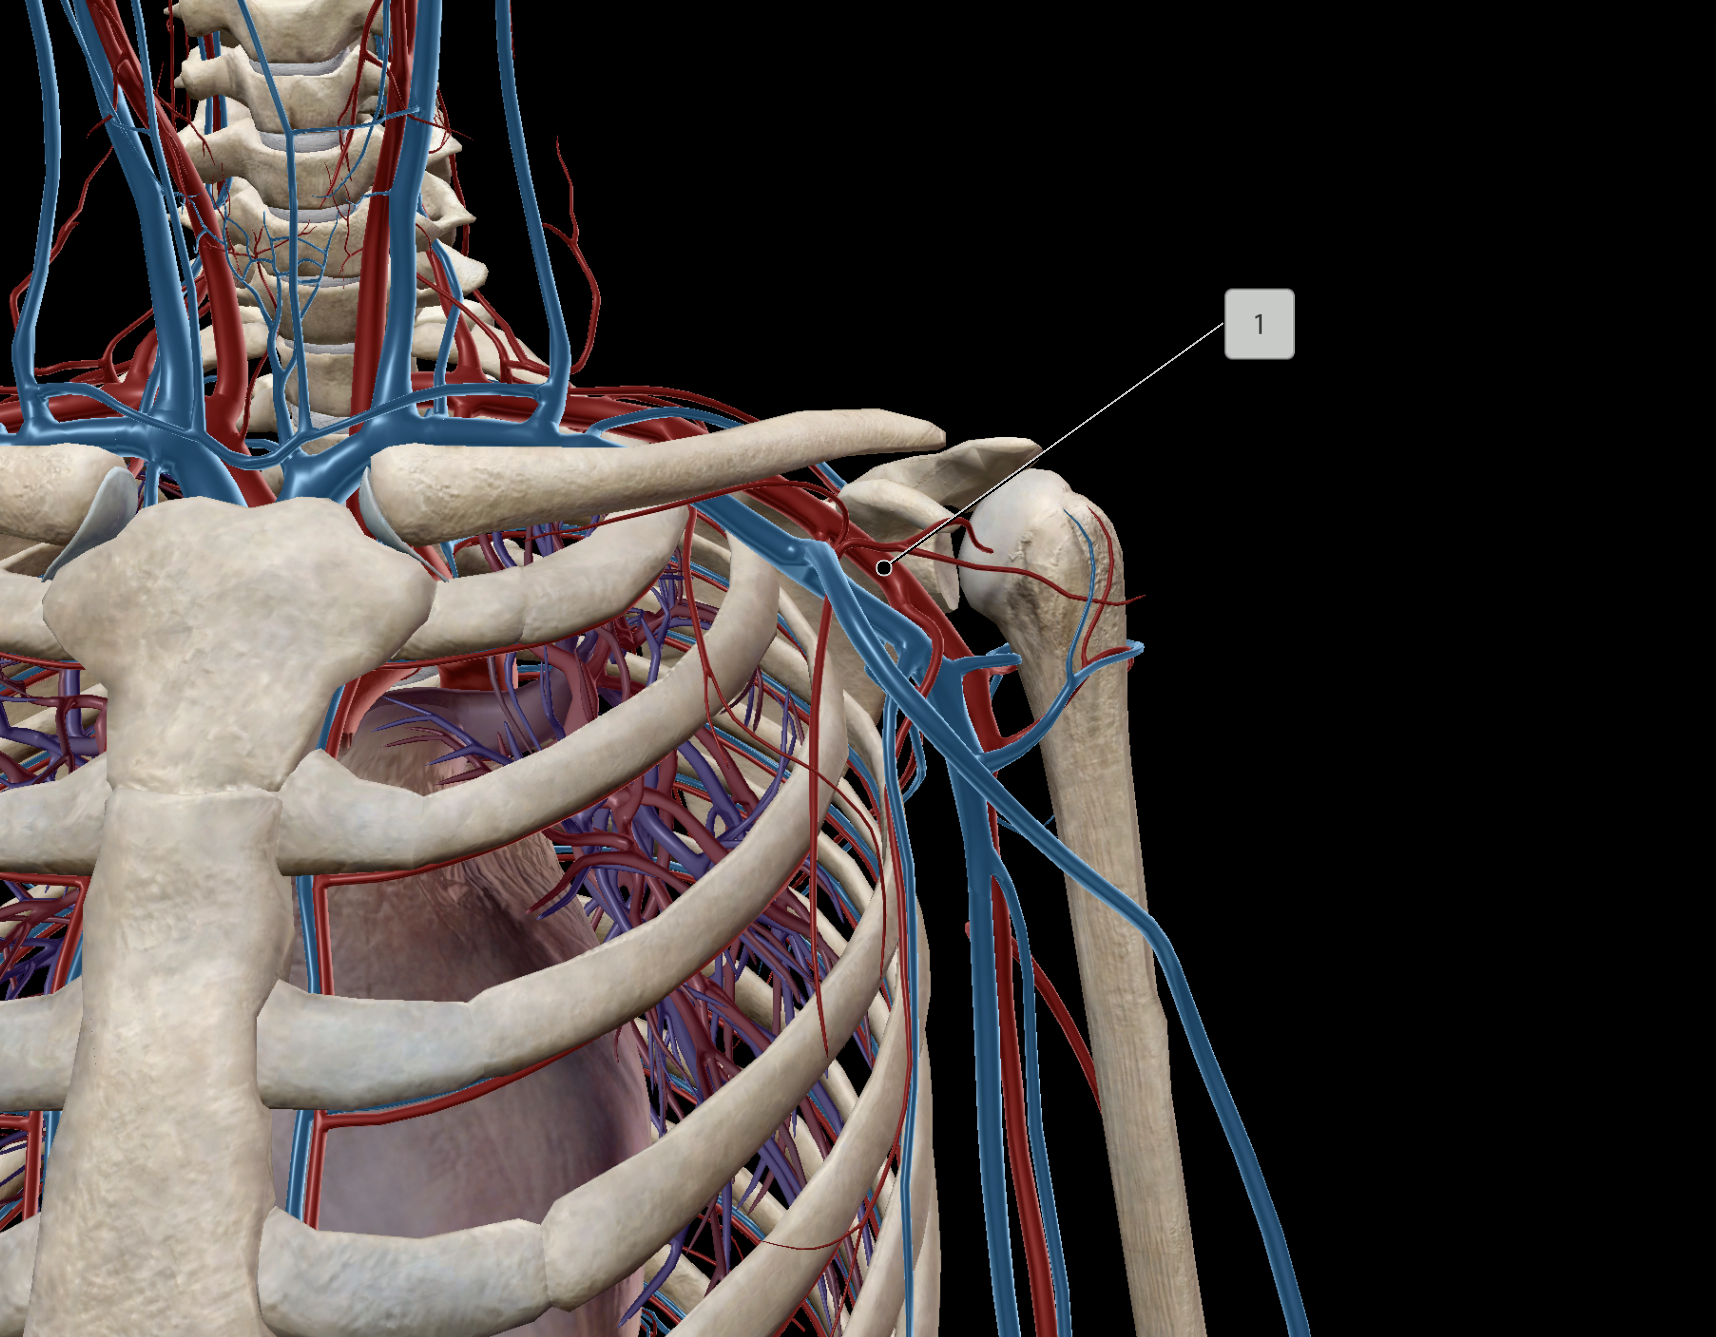

Axillary Artery

Axillary Vein